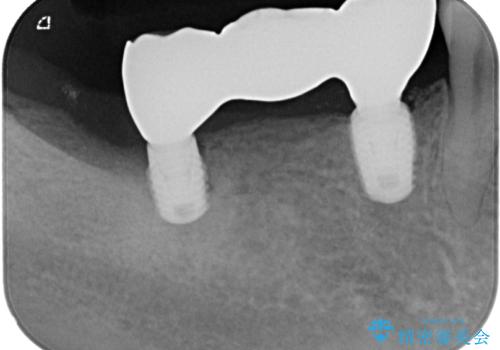

ブリッジの支台歯2本を抜歯し、反対側の咬合負担を軽減するために、通常よりも短い待機時間で2本のインプラントを埋入することとしました。

インプラントは、根管治療をした歯と比べると、破折するリスクは圧倒的に低いですが、こちらの方のように、臼歯しか咬合していない場合、歯ぎしりによる負担でインプラント周辺の骨が吸収する可能性があります。

就寝時のマウスピースの装着と定期的な通院によるレントゲン撮影や咬み合わせのチェックが必須となります。